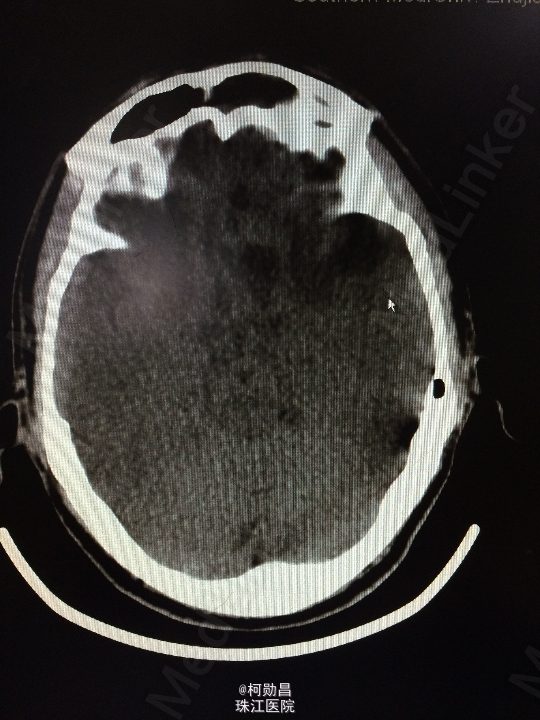

主诉:头痛伴左眼视力下降半年 病史:患者46岁男性,缘于半年前无明显诱因出现头痛,当时未予特殊处理,后症状进行性加重,并发左眼视力下降,于当地医院行头颅CT及MR检查提示颅内占位,为进一步治疗而入我院。 既往病史:5年前曾患鼻咽癌

查体:神志清楚,对答流利,左侧眼裂变小,左侧瞳孔散大,直径4mm,对光反射迟钝,左眼视力下降。右侧正常。 辅助检查:头颅MR提示前颅底筛沟通病变

诊断:鼻咽癌脑转移 处理:全麻下行颅筛沟通占位切除术,术后病理提示:鼻咽非角化鼻咽癌脑转移